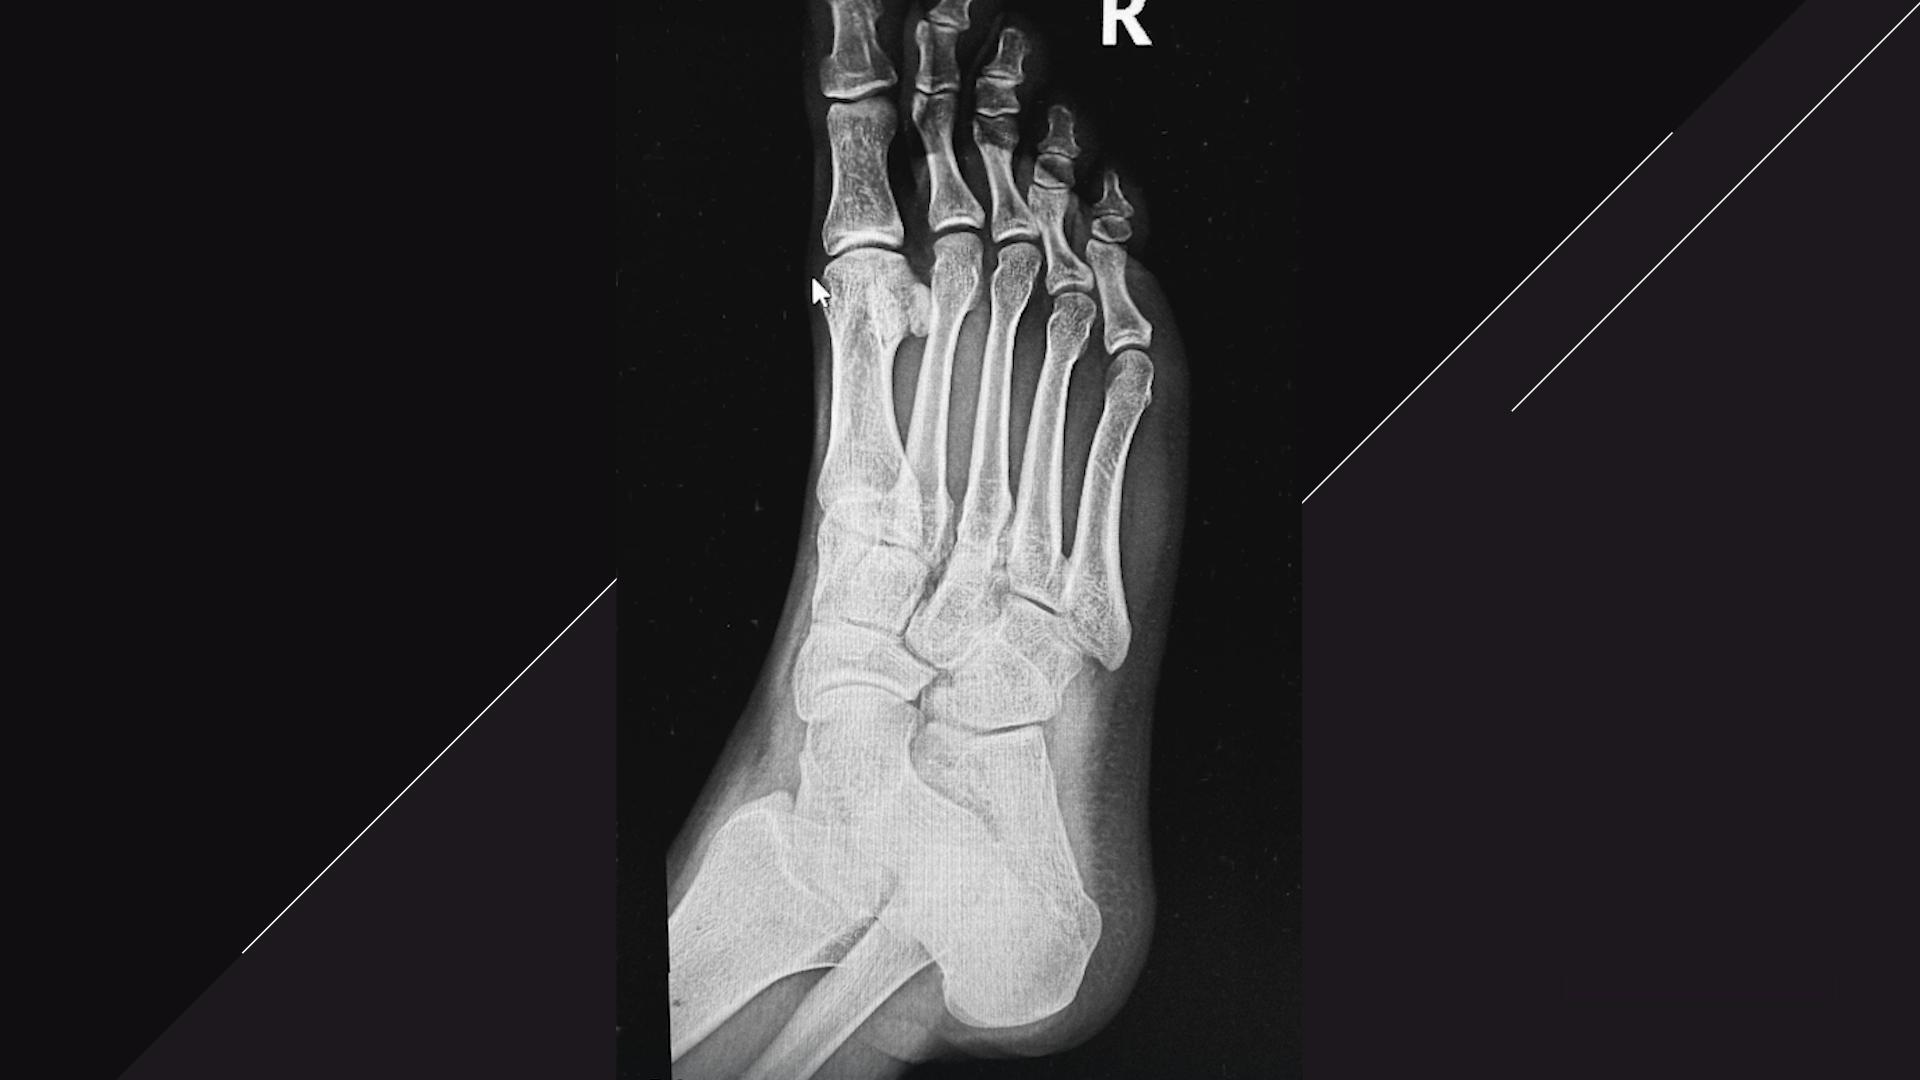

По словам рэпера, его ногу сильно раздуло, но обошлось без перелома костей.

Крид записался на МРТ и ему сообщили, что у него порваны сухожилия на ноге спереди и сзади.